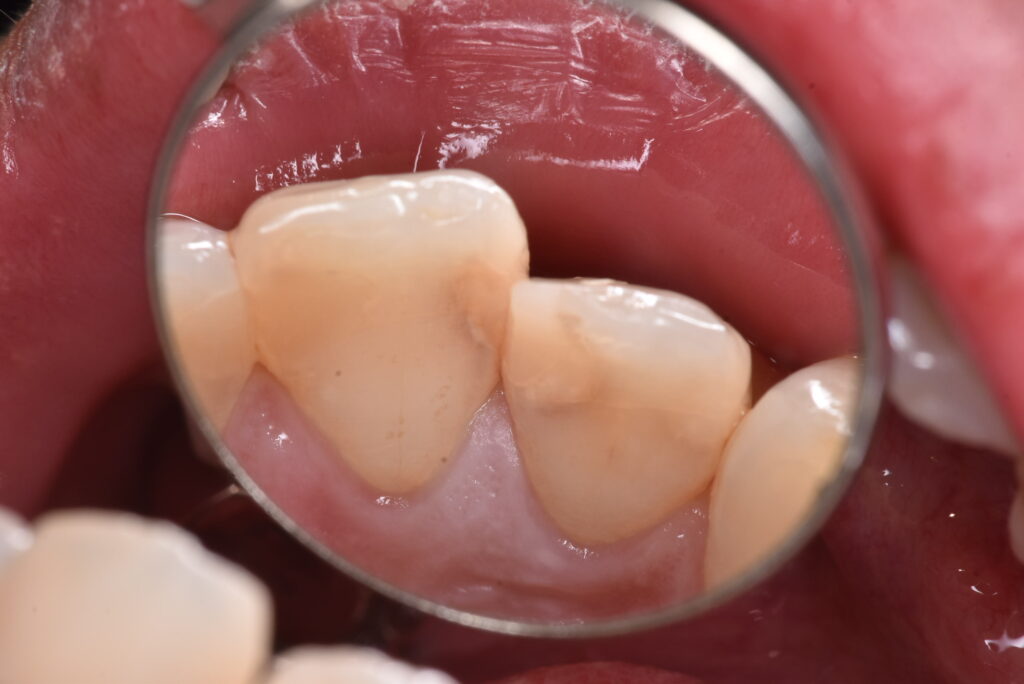

白のつめもののなかの一例

実際の処置例をお見せしていきます。。

処置する前から、怪しい状態なのはなんとなくわかると思います。では、この方は症状はあったのか?

→Noです。ありませんでした。つめものの周りに隙間があったのか?それもNoです。

削った写真を見ていただくと、中で汚染されている部分がわかると思います。一番最後の写真の中央にあるのは、むし歯の部分ではなく、神経の入り口です。神経は基本的に歯の奥の方に隠れています。むし歯を取り除くとそれが見える・・・それは正常なことなのでしょうか?